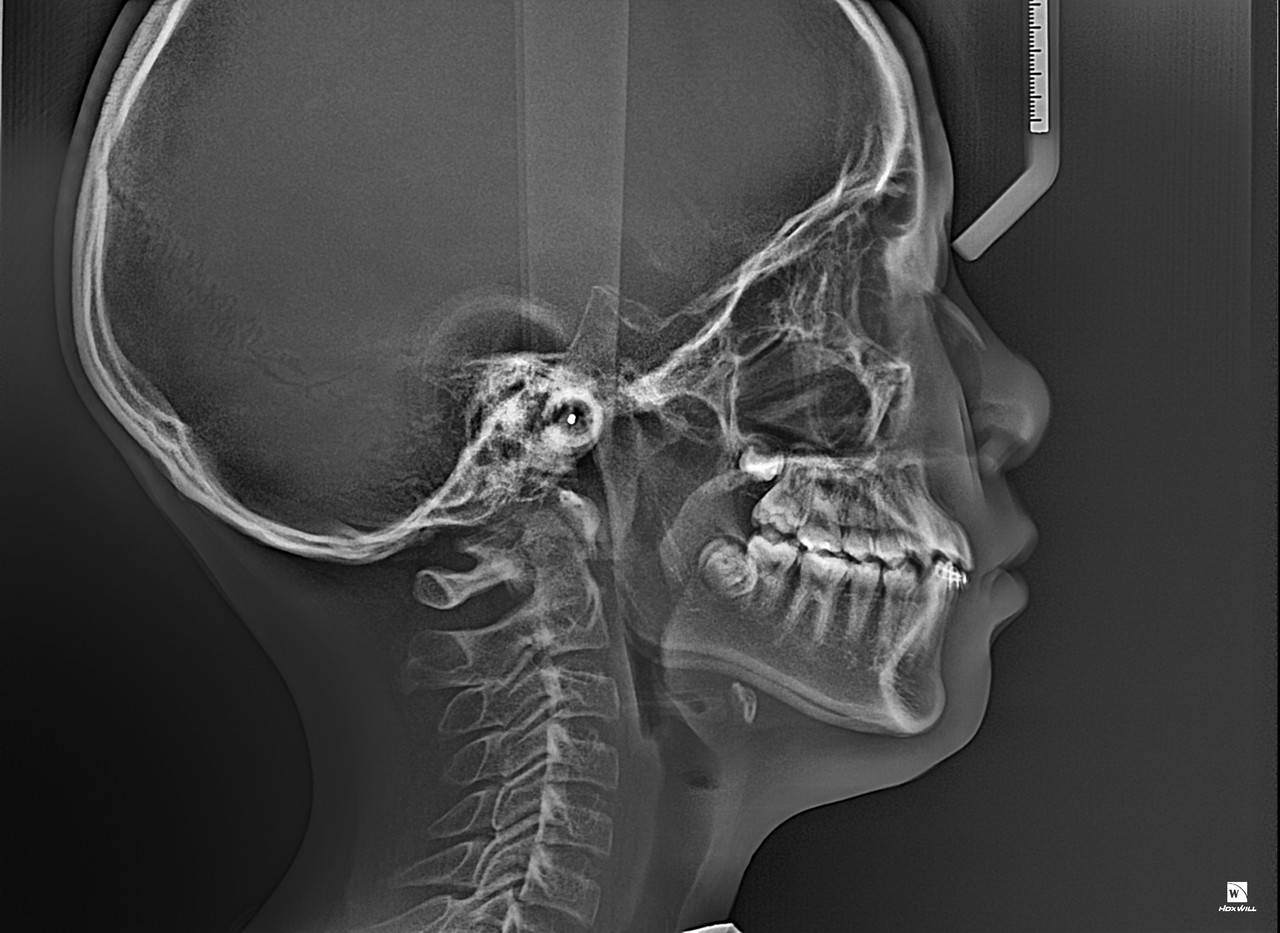

프리올소(Pre-Ortho)는 "Pre Orthodontics"의 줄임말로,

어린이의 턱 성장과 치열 발달을 돕는 조기 예방 교정치료를 뜻합니다.

일반적으로 영구치가 완전히 나오기 전인 6세~12세 어린이를 대상으로 하며,

브라켓(교정기) 없이 기능성 장치를 활용해 턱·치열의 정상 성장을 유도하는 것이 핵심입니다.

[하악 반대교합이였던게 개선된 모습]

BEFORE

[Edge to edge bite (절단끼리 맞물리는 교합)]

페이스마스크

페이스마스크(Facemask)는 얼굴 바깥쪽에 착용하는 교정 장치로,

위턱이 앞으로 자라도록 유도하는 데 사용됩니다.

주로 성장기 어린이(초등학생 전후)에게 적용되며,

주걱턱(반대교합)을 조기에 개선하는 데 매우 효과적입니다.

01

주걱턱을 수술 없이 치료할 수 있는 비수술적 방법

02

턱 성장 방향을 바꿔서 자연스러운 얼굴형 유도

03

나중에 진행할 수 있는 2차 교정의 난이도 감소